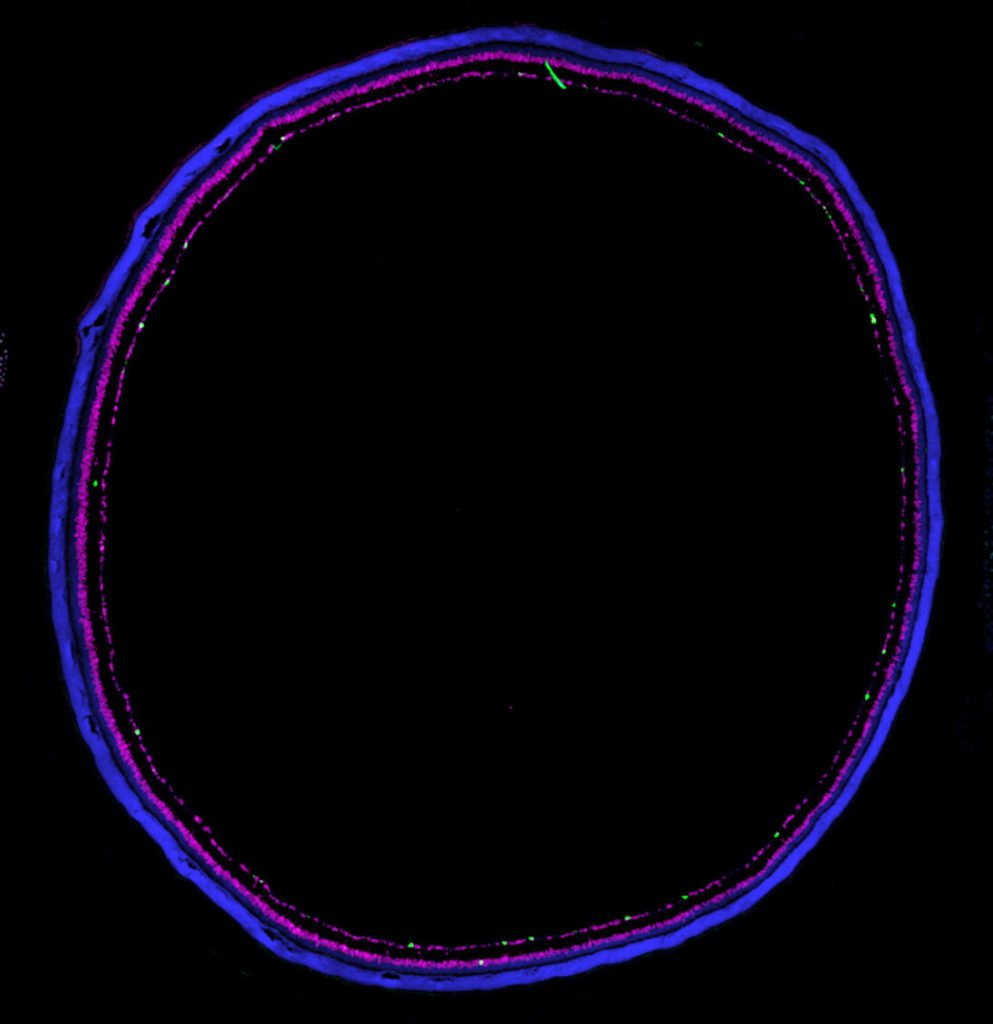

Fig 1. Retinal section from a mouse where cell nuclei are labelled in blue, inhibitory cells is labelled with magenta, and ipRGCs are labelled in green.

Image from a mouse retinal section where cell nuclei are labelled in blue, RNA for the GABA synthesis enzyme Gad2 is labelled in magenta, and RNA for melanopsin is labelled in green. Credit: Northwestern University.

Fig 2. Image from a mouse retinal section where cell nuclei are labelled in blue, RNA for the GABA synthesis enzyme Gad2 is labelled in magenta, and RNA for melanopsin is labelled in green.